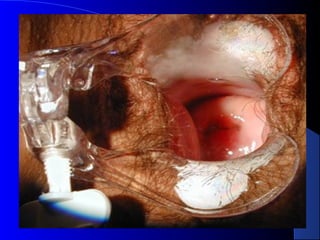

COLO DO ÚTERO NORMALCOLO DO ÚTERO NORMAL

COLO DO ÚTERONORMALCOLO DO ÚTERO NORMAL